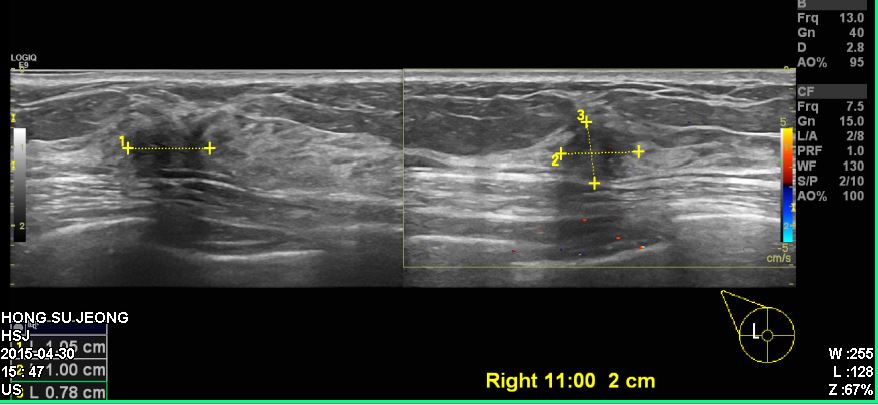

건강검진상 이상 소견으로 내원하신 50대 여성 분으로 우측 침윤성 유관암

진단 되었습니다.